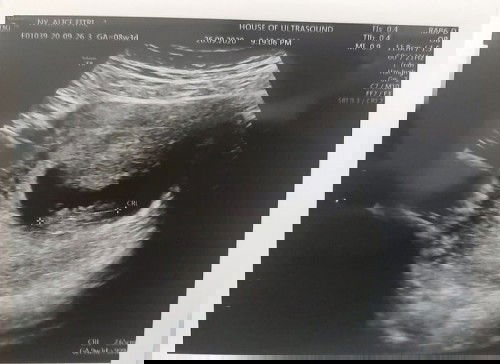

Usia Kehamilan Hpht dan Usg

Halo bunda semuaa.. ini kehamilan pertama ku dan baru pertama kali usg. Yang mau sy tanyakan nih bun, umur kehamilan yg benar itu menurut usg atau menurut hpht yaa? Kemaren sy ke dokter katanya janin sy seperti umur 9w3d dan dikira salah ngasih tanggal hpht malah hehehe (klo menurut hph 8w3d). Mungkin bisa dilihat di foto usg GA (atas dan kanan bawah berbeda). Tapi sy inget bgt klo tgl hpht sy bener krn siklusnya tepat 28 hari. Siapatau bunda disini bisa kasih saya pencerahan hihiw makasiiii sebelumnya.